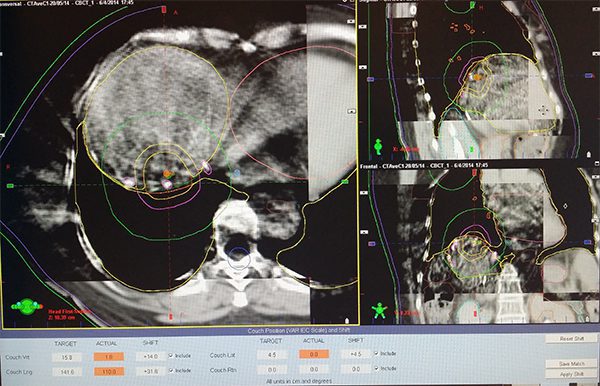

Stereotactic Body Radiation Therapy (SBRT) refers to an advanced form of external beam radiotherapy. A specialised co-ordinate system allows multiple, sharply focussed x-ray beams to hit small targets in the body. This not only allows liver tumors to be treated with great precision (therefore minimizing collateral damage), but also allows the delivery of high doses of radiation to a target within the body in either one or up to five treatment sessions. With such technology, this non-invasive method of delivering radiotherapy is now recognized as one of the options for treating liver tumours. SBRT can be employed to treat both primary and secondary liver tumours, especially those deemed not suitable for surgical removal.